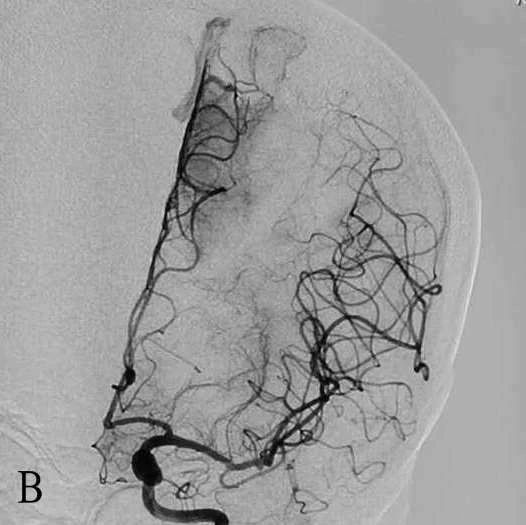

B:左侧ICA造影正位示前交通未开放

D:取栓后右侧ICA造影正位示mTICI2b级再通